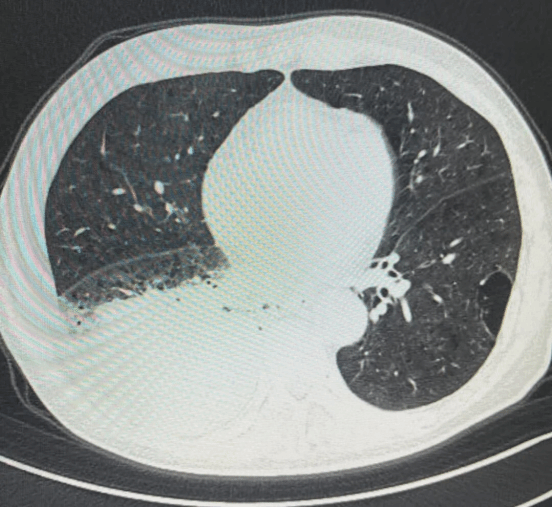

依托医学影像设备,实时可视化引导穿刺针精准抵达病灶,避开血管、神经等重要结构。

• CT室专家与呼吸团队紧密协作,精准定位,并准确调整穿刺角度,确保穿刺针精准命中病灶。